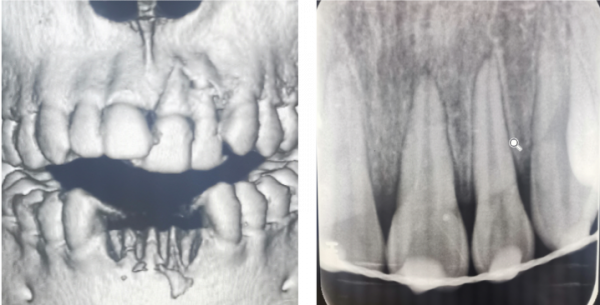

根折--根頸1/3

治療方案:復位鬆動移位的牙冠,夾板固定4周,折斷線近牙頸部固定時間延至4個月,定期檢測折斷線癒合情況,監測牙髓狀態。牙髓壞死或感染則進行冠方的牙髓治療。如頸部折斷後斷片異常鬆動,治療則同冠根折。

根折--根中1/3

治療方案:復位鬆動移位的牙冠,夾板固定4周,定期檢測折斷線癒合情況,監測牙髓狀態。牙髓壞死或感染則進行冠方的牙髓治療。

根折--根尖1/3

治療方案:復位鬆動移位的斷片,彈性夾板固定4周,定期檢測折斷線癒合情況,監測牙髓狀態。牙髓壞死或感染則進行冠方的牙髓治療。